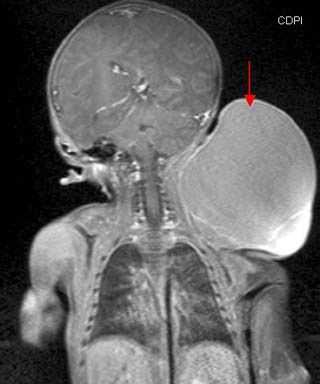

(Справа) МРТ, постконтрастные Т1ВИ, аксиальный срез: определяется небольшое контрастирование контуров и перегородки образования. Гиперинтенсивный сигнал внутри кистозных областей образования визуализировался до введения гадолиния, вероятнее всего, вследствие повышенного накопления белков. (Слева) МРТ Т2ВИ, режим подавления сигнала от жира, коронарный срез: определяется очень крупное экзофитное образование, выпячивающееся из латеральной поверхности грудной стенки и стенки живота слева. Образование содержит множественные перегородки. Общая интенсивность сигнала высокая, но не такая как ожидалось при простом скоплении жидкости.

4. МРТ при лимфангиоме:

• Многокамерное образование с перегородками, имеющее гетерогенную интенсивность сигнала

• Большая часть образования имеет жидкостной сигнал:

о Гиперинтенсивный сигнал на Т1 ВИ может быть вызван кровоизлиянием или наличием белковой жидкости

о Жидкостно-жидкостные уровни, вследствие наличия детрита в кистозных областях

• Стенка образования и перегородка имеют умеренную или низкую интенсивность сигнала и немного накапливают контраст